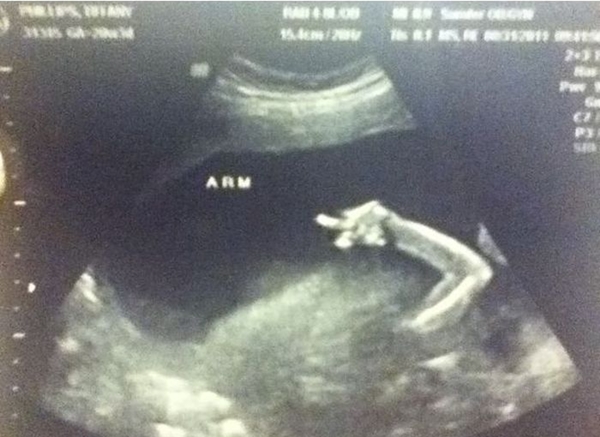

Tương lai em bé này sẽ là một cậu bé nghịch lắm đây.

Tương lai em bé này sẽ là một cậu bé nghịch lắm đây.